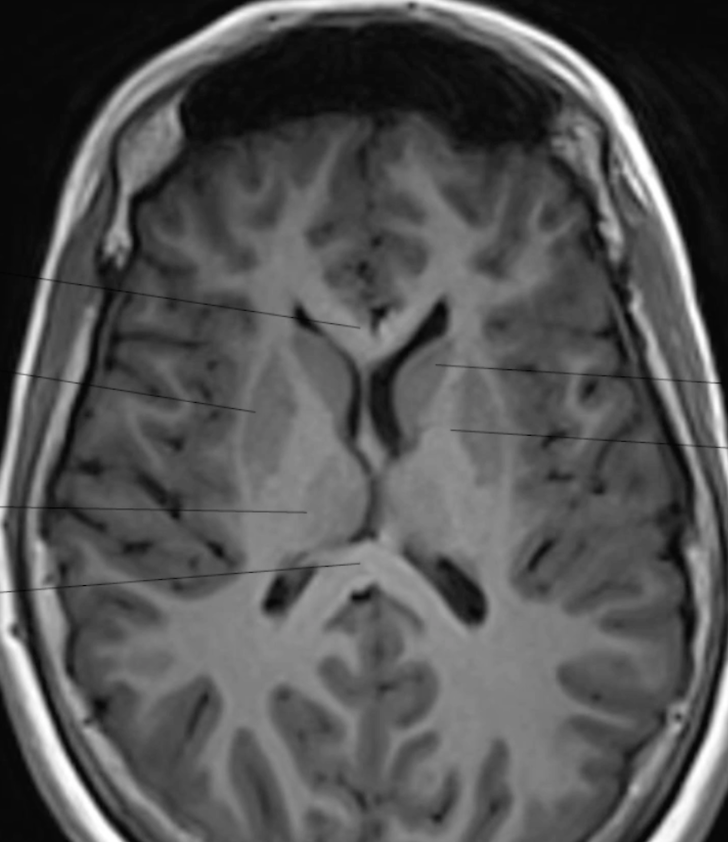

Quelle est la séquence de cet IRM ? + décris l’anatomie